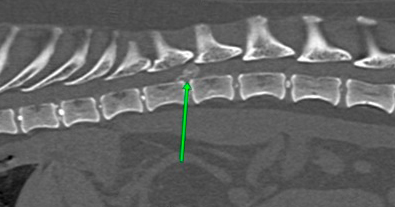

Scanner